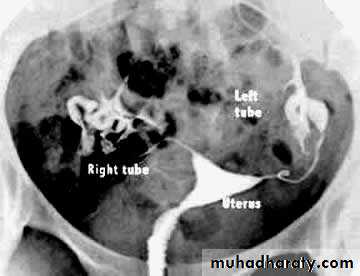

Hysterosalpingogram

Hysterosalpingogram (HSG) is a fluoroscopic examination of the uterus and theFallopian tubes, most commonly used in the investigation of infertility or recurrent spontaneous abortions.

HSG showing a normal uterus and blocked tubes No "spill" of dye is seen at the ends of the tubes Both tubes are slightly dilated and fluid filled - hydrosalpinxHSG : fibroid is pushing in to the uterus cavity